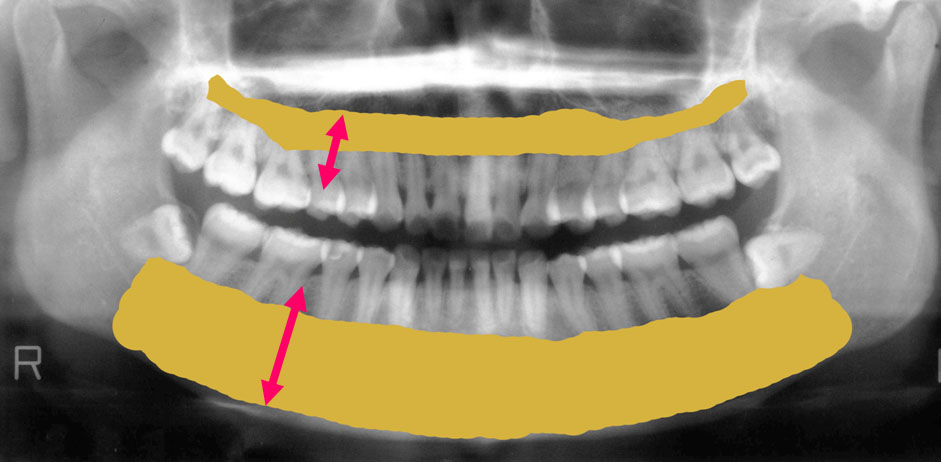

歯を支えている骨部分が今はこれだけの量があります。

しかし骨が少なくなるとこんな風になってしまうのです。